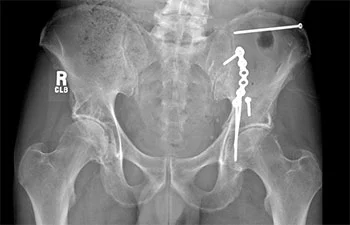

Pelvic fractures involve a break in the pelvic bones, which can result from high-impact injuries such as accidents or falls. Acetabulum fractures affect the socket of the hip joint, often leading to mobility issues and severe pain. These fractures require expert evaluation and a personalized treatment plan to restore function and prevent long-term complications.

At Numed Hospital, we use advanced imaging techniques such as CT scans, MRI, and digital X-rays to accurately assess the extent of the injury. Our treatment options include:

At Numed Hospital, we prioritize patient care with a multidisciplinary approach, ensuring faster recovery and long-term well-being. Our orthopedic team is experienced in handling severe pelvic and acetabulum fractures with precision and expertise. As the Best Orthopedic Hospital in Greater Noida, we are committed to providing world-class treatment and compassionate care to help you regain an active lifestyle.